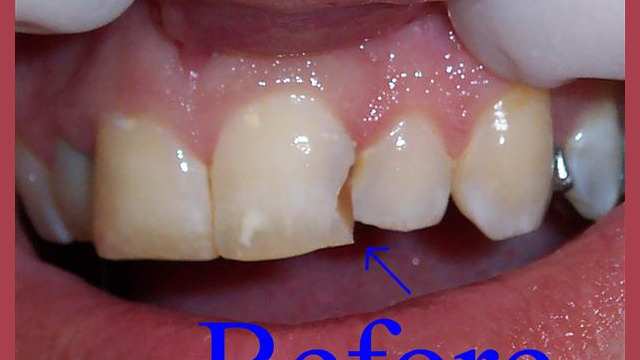

Dental Bonding

Restorative dentistry services focus on repairing teeth damaged to cavities, tooth decay, or trauma. From our beginning, it has been our goal to help our patients restore strength and structure to their smiles. We are committed to helping your smile stay beautiful and healthy for a lifetime. We incorporate the latest dental technology to ensure you receive the most advanced care. Our restorative services include: